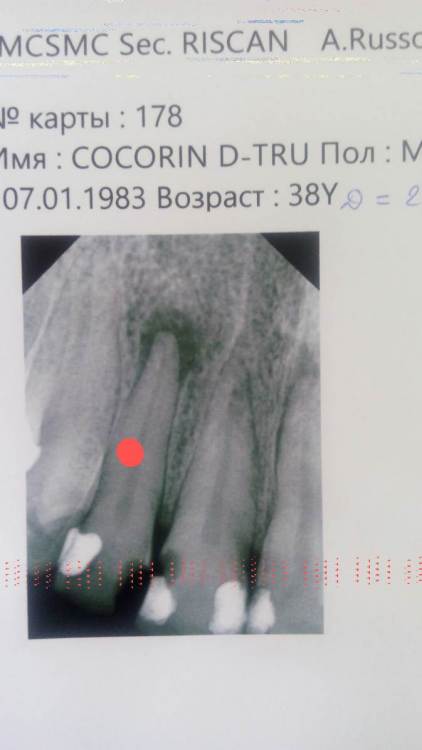

Dmitry1983 Опубликовано 15 сентября, 2021 Поделиться Опубликовано 15 сентября, 2021 (изменено) Здравствуйте. Есть ли показания к резекции корней судя по снимкам? Зубы отмечены красным маркером. Передние верхние. Изменено 15 сентября, 2021 пользователем Dmitry1983 Ссылка на комментарий

Irouil Опубликовано 15 сентября, 2021 Поделиться Опубликовано 15 сентября, 2021 Зубы, отмеченные красным, надо лечить у терапевта классическим доступом, на мой взгляд 1 Ссылка на комментарий

Irouil Опубликовано 15 сентября, 2021 Поделиться Опубликовано 15 сентября, 2021 Классический (ортоградный) доступ - это доступ через коронковую часть зуба (лечение корня через зуб) Резекция Верхушки Корня (РВК) предполагает пломбировку канала корня обратным (ретроградным) доступом, через его верхушку. Используется эта методика тогда, когда ортоградный доступ отсутствует (на зубе коронка с вкладкой или зуб запломбирован неизвлекаемым материалом) 1 Ссылка на комментарий

St. Опубликовано 15 сентября, 2021 Поделиться Опубликовано 15 сентября, 2021 Добрый день. Сейчас показаний к резекции нет. Нужно качественно полечить каналы, и только если через 6-12 мес.после этого не будет улучшений по снимкам(что при хорошем эндо бывает редко) планировать резекцию. 1 1 Ссылка на комментарий

Bier Опубликовано 21 сентября, 2021 Поделиться Опубликовано 21 сентября, 2021 все верно сказали, показаний для РВК сейчас нет 1 Ссылка на комментарий